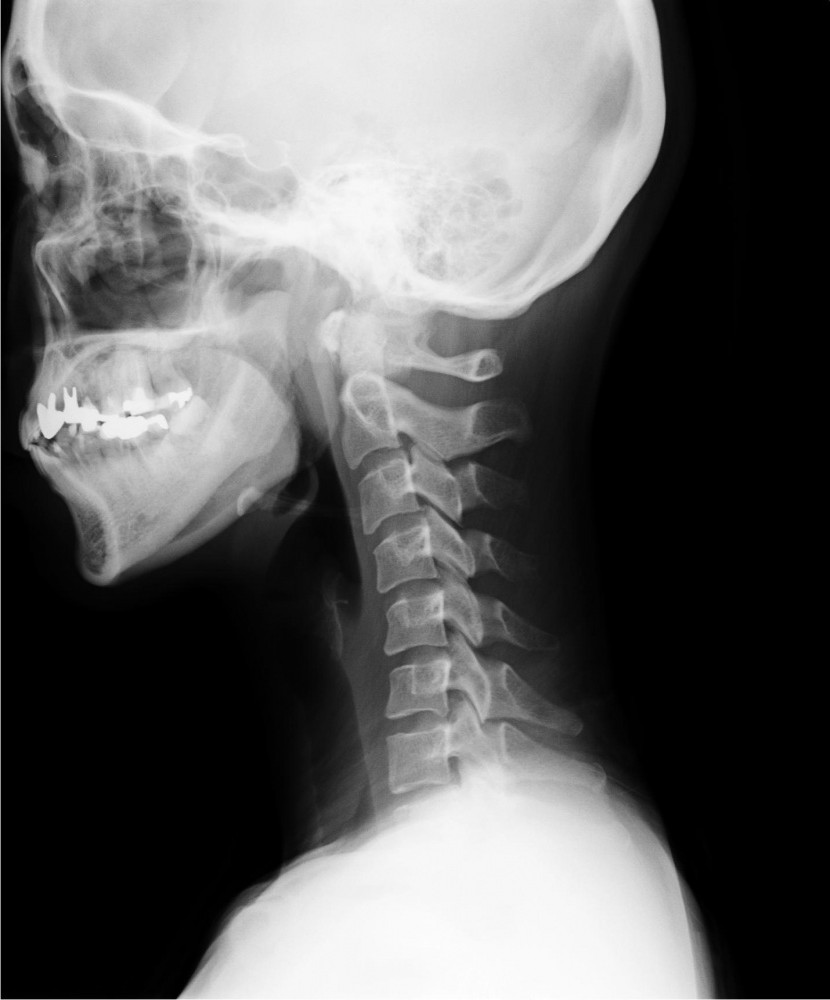

側面像

【内容】

・頸椎正面像(開口像)、頸椎側面像

レントゲン画像を見ると背骨のゆがみやズレなども大切なのですが、実際には背骨のズレは、骨折・脱臼・靭帯の断裂などが無い限り存在しないのです。

私たちカイロプラクターがレントゲンで着目している個所は「椎間板」です。

「椎間板」の変性により椎骨が傾くことで、背骨のゆがみやストレートネックなどが現れます。

毎日の生活環境によって背骨の形状は変化していきます。下を向くようなデスクワークや家事のような環境では、頭部は前方に移動します。

その前方に移動した頭部に対して、バランスをとるために頚椎のカーブは後ろに移動します。結果、環境に適応するためにストレートネックになるのです。